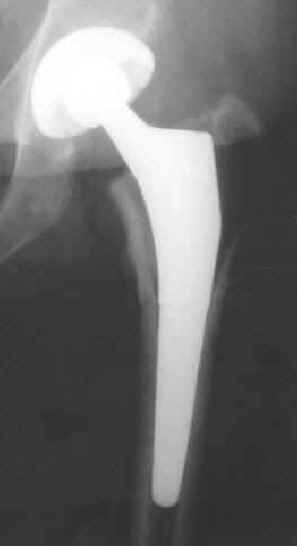

Titanium hip implant

Courtesy Ed Mullin